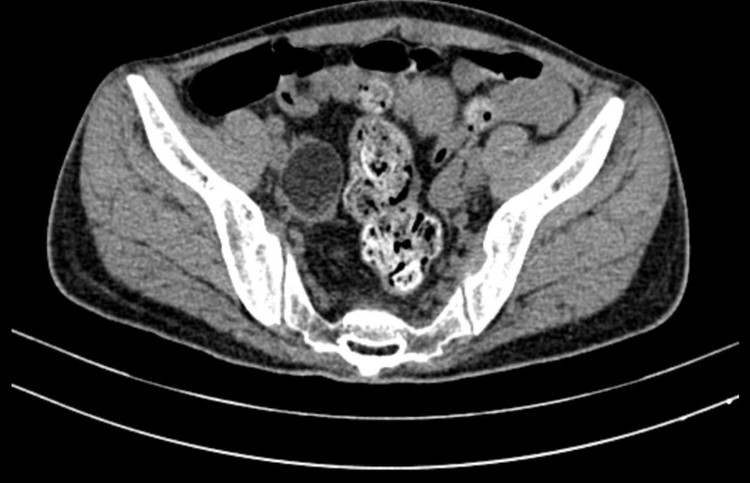

Ngay lập tức cuộc hội chẩn giữa hai chuyên Khoa Nội thần kinh và Hồi sức tích cực được diễn ra nhanh chóng, hỗ trợ tối đa để người bệnh được thay huyết tương và khảo sát các nguyên nhân như ung thư, u quái phần phụ và kịp thời phát hiện khối u ở buồng trứng.

Kết quả sinh thiết tế bào dưới kính hiển vi cho thấy đây là u quái buồng trứng, một trong các nguyên nhân gây bệnh viêm não tự miễn kháng thể kháng thụ thể NMDA ở phụ nữ. Sau khi điều trị loại bỏ các kháng thể tích cực và tình trạng người bệnh ổn định hơn, việc phẫu thuật cắt bỏ u để ngăn chặn bệnh diễn tiến được lên kế hoạch chi tiết cùng với chuyên khoa Sản phụ khoa.

Hình ảnh khối u quái buồng trứng bên phải |

TS.BS. Trịnh Hồng Hạnh, Chủ nhiệm khoa Sản cho biết: “Đây là một ca bệnh viêm não tự miễn do tự kháng thể kháng thụ thể NMDA khá điển hình theo y văn, việc phẫu thuật loại bỏ u buồng trứng là một trong những điều trị cốt lõi giúp lui bệnh và ngăn ngừa tái phát”.

Cuối cùng sau 7 lần thay huyết tương, người bệnh được phẫu thuật nội soi cắt u quái. Ca mổ diễn ra an toàn và thành công tuyệt đối, người bệnh hồi mê nhanh chóng trong cùng ngày phẫu thuật.

Hình ảnh khối u quái buồng trứng bên phải